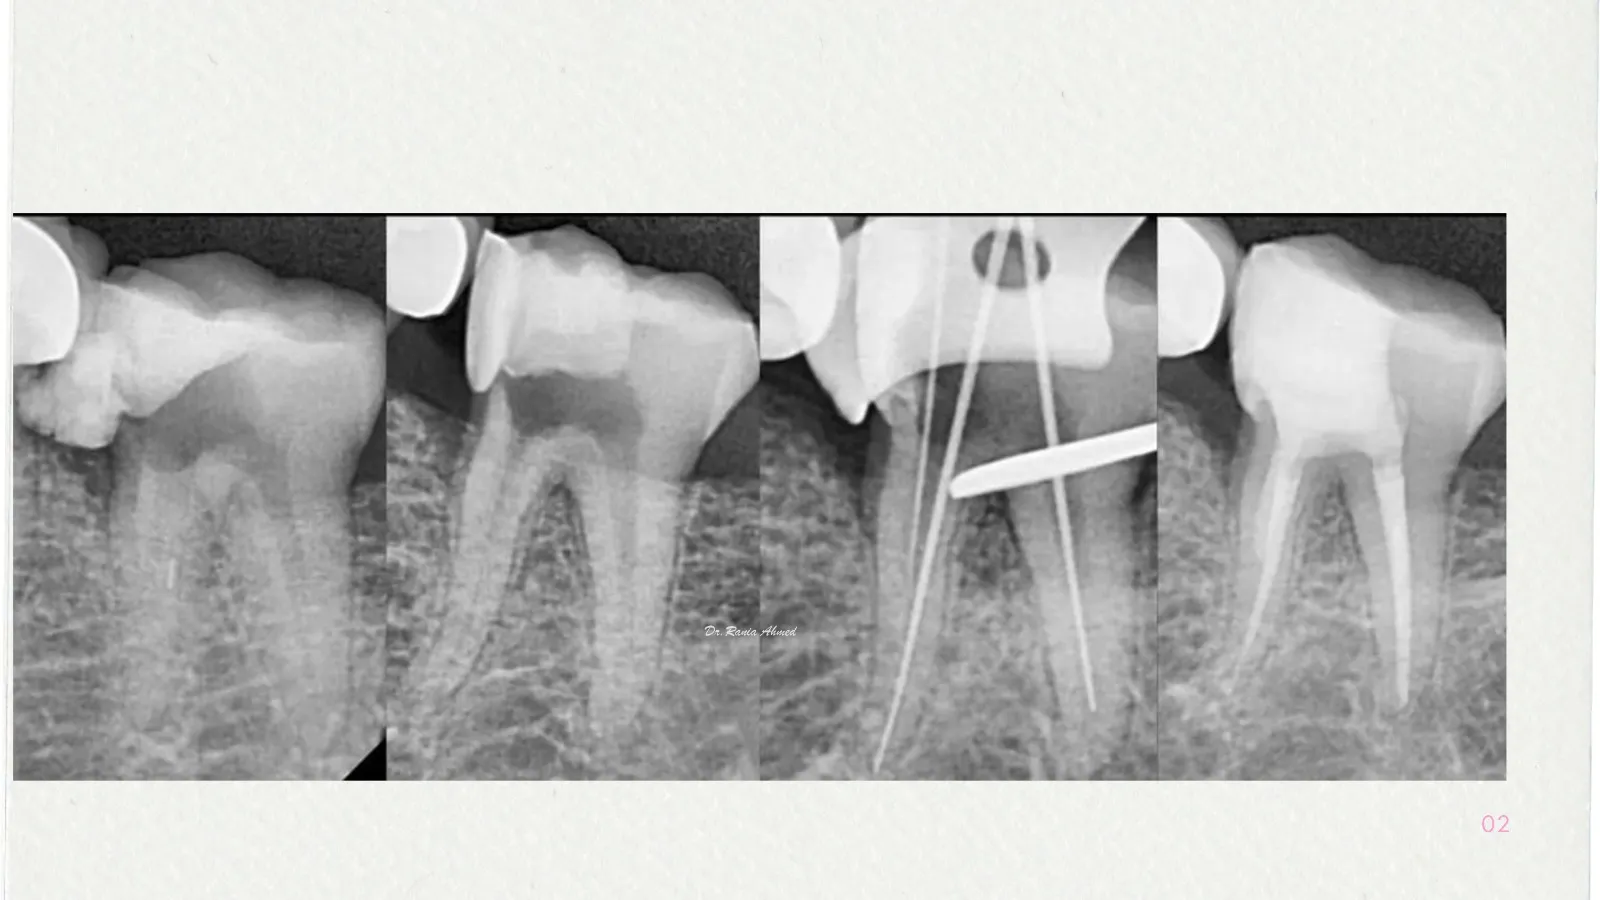

Endodontic Treatment